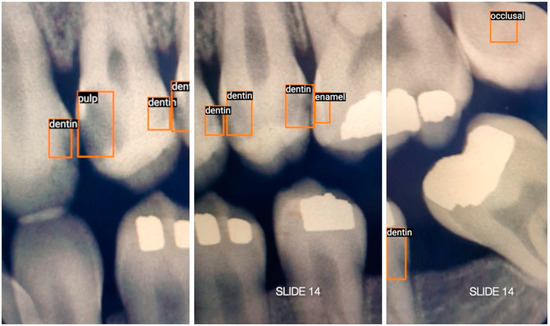

英文标题: Real-Time Caries Detection of Bitewing Radiographs Using a Mobile Phone and an Artificial Neural Network: A Pilot Study

中文标题:基于手机与人工神经网络的咬翼片实时龋齿检测:一项初步研究

文章链接:https://www.mdpi.com/2673-6373/3/3/35

英文标题: One-Stage Methods of Computer Vision Object Detection to Classify Carious Lesions from Smartphone Imaging

中文标题: 基于单阶段计算机视觉目标检测的智能手机影像龋损识别方法

文章链接:https://www.mdpi.com/2673-6373/3/2/16